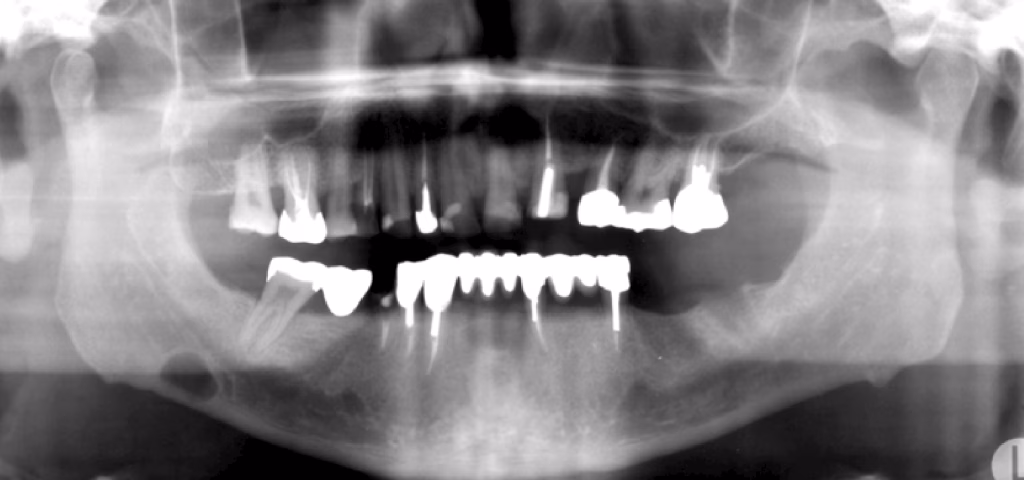

Some “cysts” don’t have a typical cyst lining — but they show up on X-rays in a way that looks similar.

These include:

1. Simple Bone Cyst

A hollow space inside the jawbone.

What to know:

- Usually found in teens or young adults

- Often shows up by accident on an X-ray

- Teeth in the area stay healthy

- Rarely causes swelling

Treatment may involve surgically checking the area, but many heal on their own.

2. Stafne Bone Defect

Not a cyst at all — just a natural indentation on the inside of the lower jaw.

3. Sinus Mucous Retention Pseudocyst

A dome-shaped bump seen inside the maxillary sinus (the air space above your upper teeth).